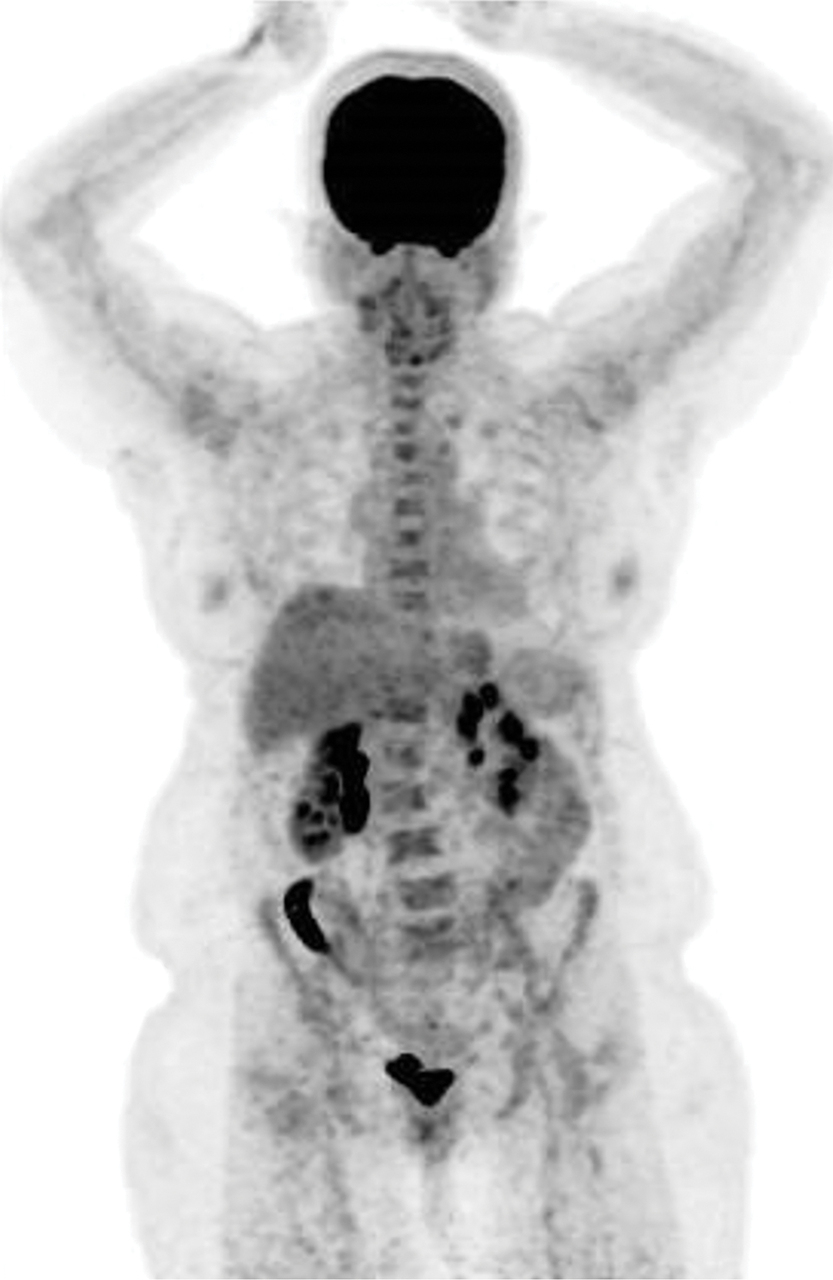

Une femme de 63 ans est hospitalisée pour une fièvre prolongée, inexpliquée, traitée à deux reprises par antibiotiques.

Quel est votre diagnostic ?